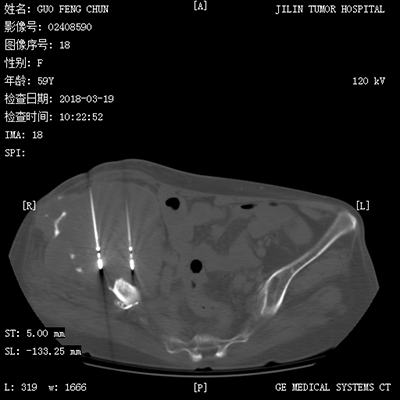

![]() | ![]() |

| (肺癌的介入治疗) | (盆腔恶性肿瘤的介入治疗) |